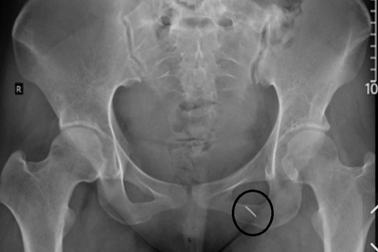

Thủ kim phòng "thượng mã phong" đêm tân hôn, cô gái bị kim chui vào ngườiCô gái 23 tuổi ở Hưng Yên được đưa đến viện trong tình trạng đau buốt khi vận động mạnh, nghi kim khâu chui vào người. Ở bệnh viện tuyến dưới, bác sĩ đã chích da nhưng không tìm thấy dị vật.